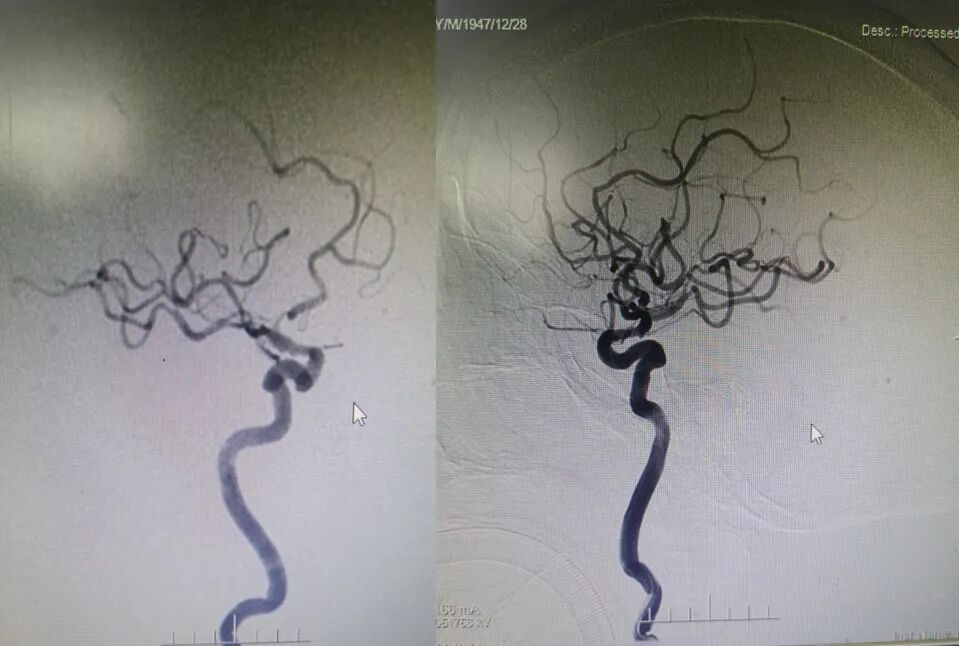

入院影像检查

导丝怎么扩【载药时代 球扩天下】NOVA DES®颅内药物洗脱支架在症状性颅内动脉狭窄中的应用—烟台鲁东医院使用体会二例!_https://www.jmylbn.com_新闻资讯_第4张

RVI

RICA

导丝怎么扩【载药时代 球扩天下】NOVA DES®颅内药物洗脱支架在症状性颅内动脉狭窄中的应用—烟台鲁东医院使用体会二例!_https://www.jmylbn.com_新闻资讯_第5张

LICA

LVI

重要影像结论:双侧颈内动脉起始段轻度狭榨,左侧椎动脉V4段重度狭窄;左侧大脑后动脉颅内段闭塞。

导丝怎么扩【载药时代 球扩天下】NOVA DES®颅内药物洗脱支架在症状性颅内动脉狭窄中的应用—烟台鲁东医院使用体会二例!_https://www.jmylbn.com_新闻资讯_第6张

LVA狭窄90%

重要影像结论:左椎动脉V4重度狭窄,大于90%,右椎动脉纤细远端闭塞。